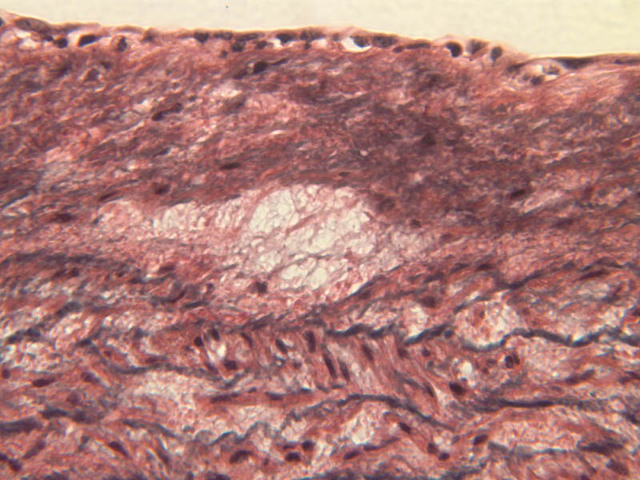

Note how extensive the elastic tissue is in the tunica media. The elastic tissue is arranged in the form of numerous concentric elastic lamellae, which are cross connected by slender elastic fibers. Observe the distribution of elastic fibers in the tunica intima (A- 27 [2.5x, 10x, 20x, 40x]) and tunica adventitia (A-27 [10x, 20x, 40x]). The internal and external elastic membranes are not well demarcated in the aorta since so many elastic lamellae are present. The elasticity of the aorta allows it to expand and absorb much of the pressure during contraction of the left ventricle (i.e., systole). When the ventricle relaxes (diastole), the elastic aorta contracts, continuing the movement of blood into the medium and muscular arteries.